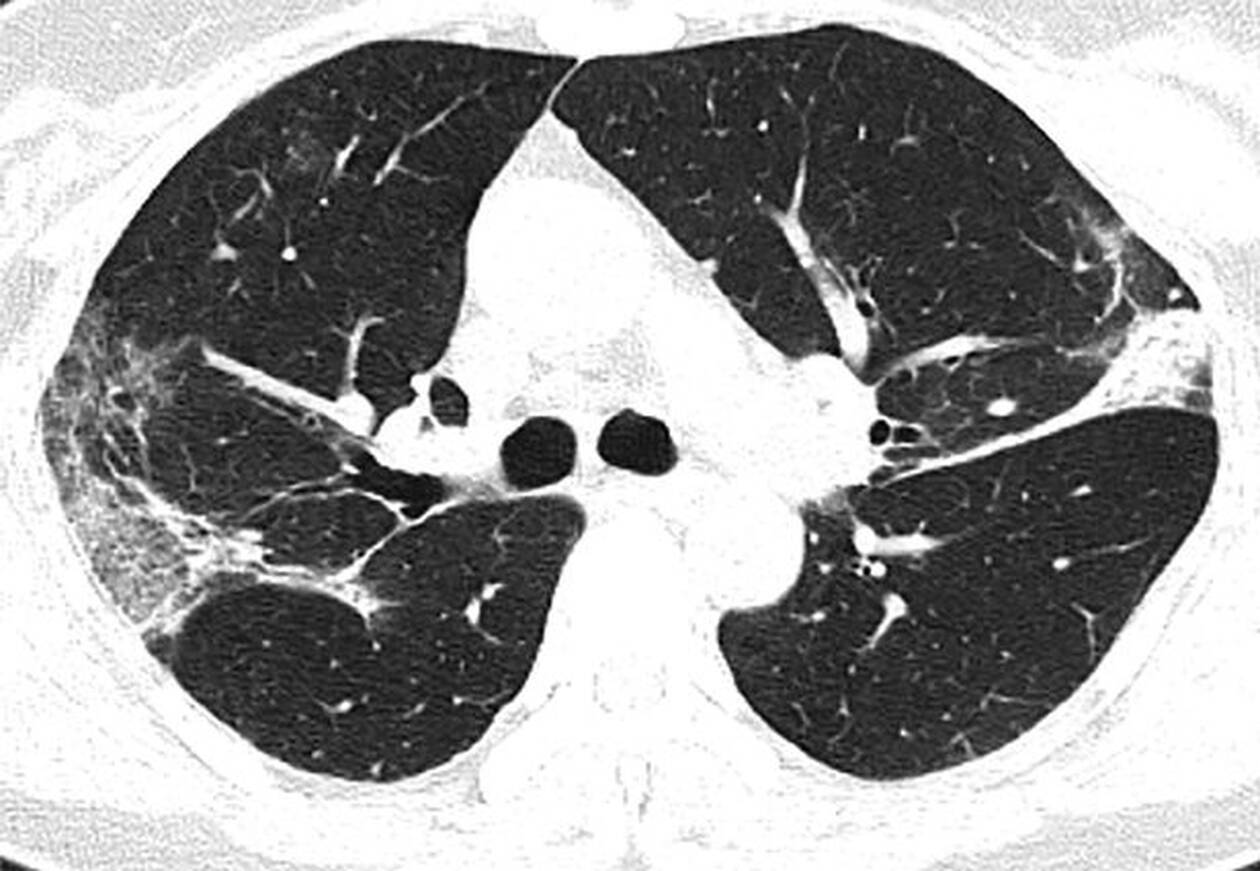

Η πανδημία του κοροναϊού covid-19 συνεχίζει να καλπάζει σε όλο τον πλανήτη, με τους γιατρούς να παρακολουθούν την έξαρσή του. Περισσότεροι από 4.000 άνθρωποι έχουν χάσει τις ζωές τους από τις επιπλοκές του ιού, ο οποίος προκαλεί σοβαρό πρόβλημα στους πνεύμονες των ασθενών. Στην δημοσιότητα δόθηκαν από την Ραδιολογική Κοινότητα της Βορείου Αμερικής ακτινογραφία πνευμόνων ασθενών, οι οποίοι είχαν προσβληθεί από τον κοροναϊό, οι οποίες προκαλούν ανατριχίλα.

Οι ασθενείς που έχουν νοσήσει μέχρι στιγμής έχουν περιγράψει την εμπειρία τους ως μια «τρομακτική προσπάθεια για να αναπνεύσουν». Στις ακτινογραφίες διακρίνονται κάποια άσπρα σημάδια, χαμηλά στους πνεύμονες. Περιγράφονται ως υγρό στις κυψέλες του πνεύμονα. Να σημειώσουμε πως οι ακτινογραφίες αυτές που δόθηκαν στην δημοσιότητα είναι από ασθενείς από την Κίνα που νόσησαν με επιπλοκές, οπότε δεν έχουν καμία σχέση με το αν νοσήσει κάποιος ο οποίος δεν αντιμετωπίζει προβλήματα υγείας.